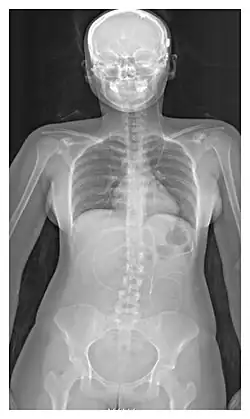

X-ray of a ventriculoperitoneal shunt

The location of the shunt is determined by the neurosurgeon based on the type and location of the blockage causing hydrocephalus. All brain ventricles are candidates for shunting. The catheter is most commonly placed in the abdomen but other locations include the heart and lungs.[11] Shunts can often be named after the route used by the neurosurgeon. The distal end of the catheter can be located in just about any tissue with enough epithelial cells to absorb the incoming CSF. Below are some common routing plans for cerebral shunts.